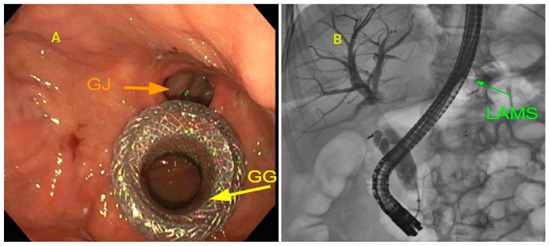

3.4. Endoscopic Ultrasound-Guided Gallbladder Drainage (EUS-GBD)

- Kedia, P.; Sharaiha, R.Z.; Kumta, N.A.; Kahaleh, M. Internal EUS-directed transgastric ERCP (EDGE): Game over. Gastroenterology 2014, 147, 566–568. [Google Scholar] [CrossRef]

- Dhindsa, B.S.; Dhaliwal, A.; Mohan, B.P.; Mashiana, H.S.; Girotra, M.; Singh, S.; Ohning, G.; Bhat, I.; Adler, D.G. EDGE in Roux-en-Y gastric bypass: How does it compare to laparoscopy-assisted and balloon enteroscopy ERCP: A systematic review and meta-analysis. Endosc. Int. Open 2020, 8, E163–E171. [Google Scholar] [CrossRef]